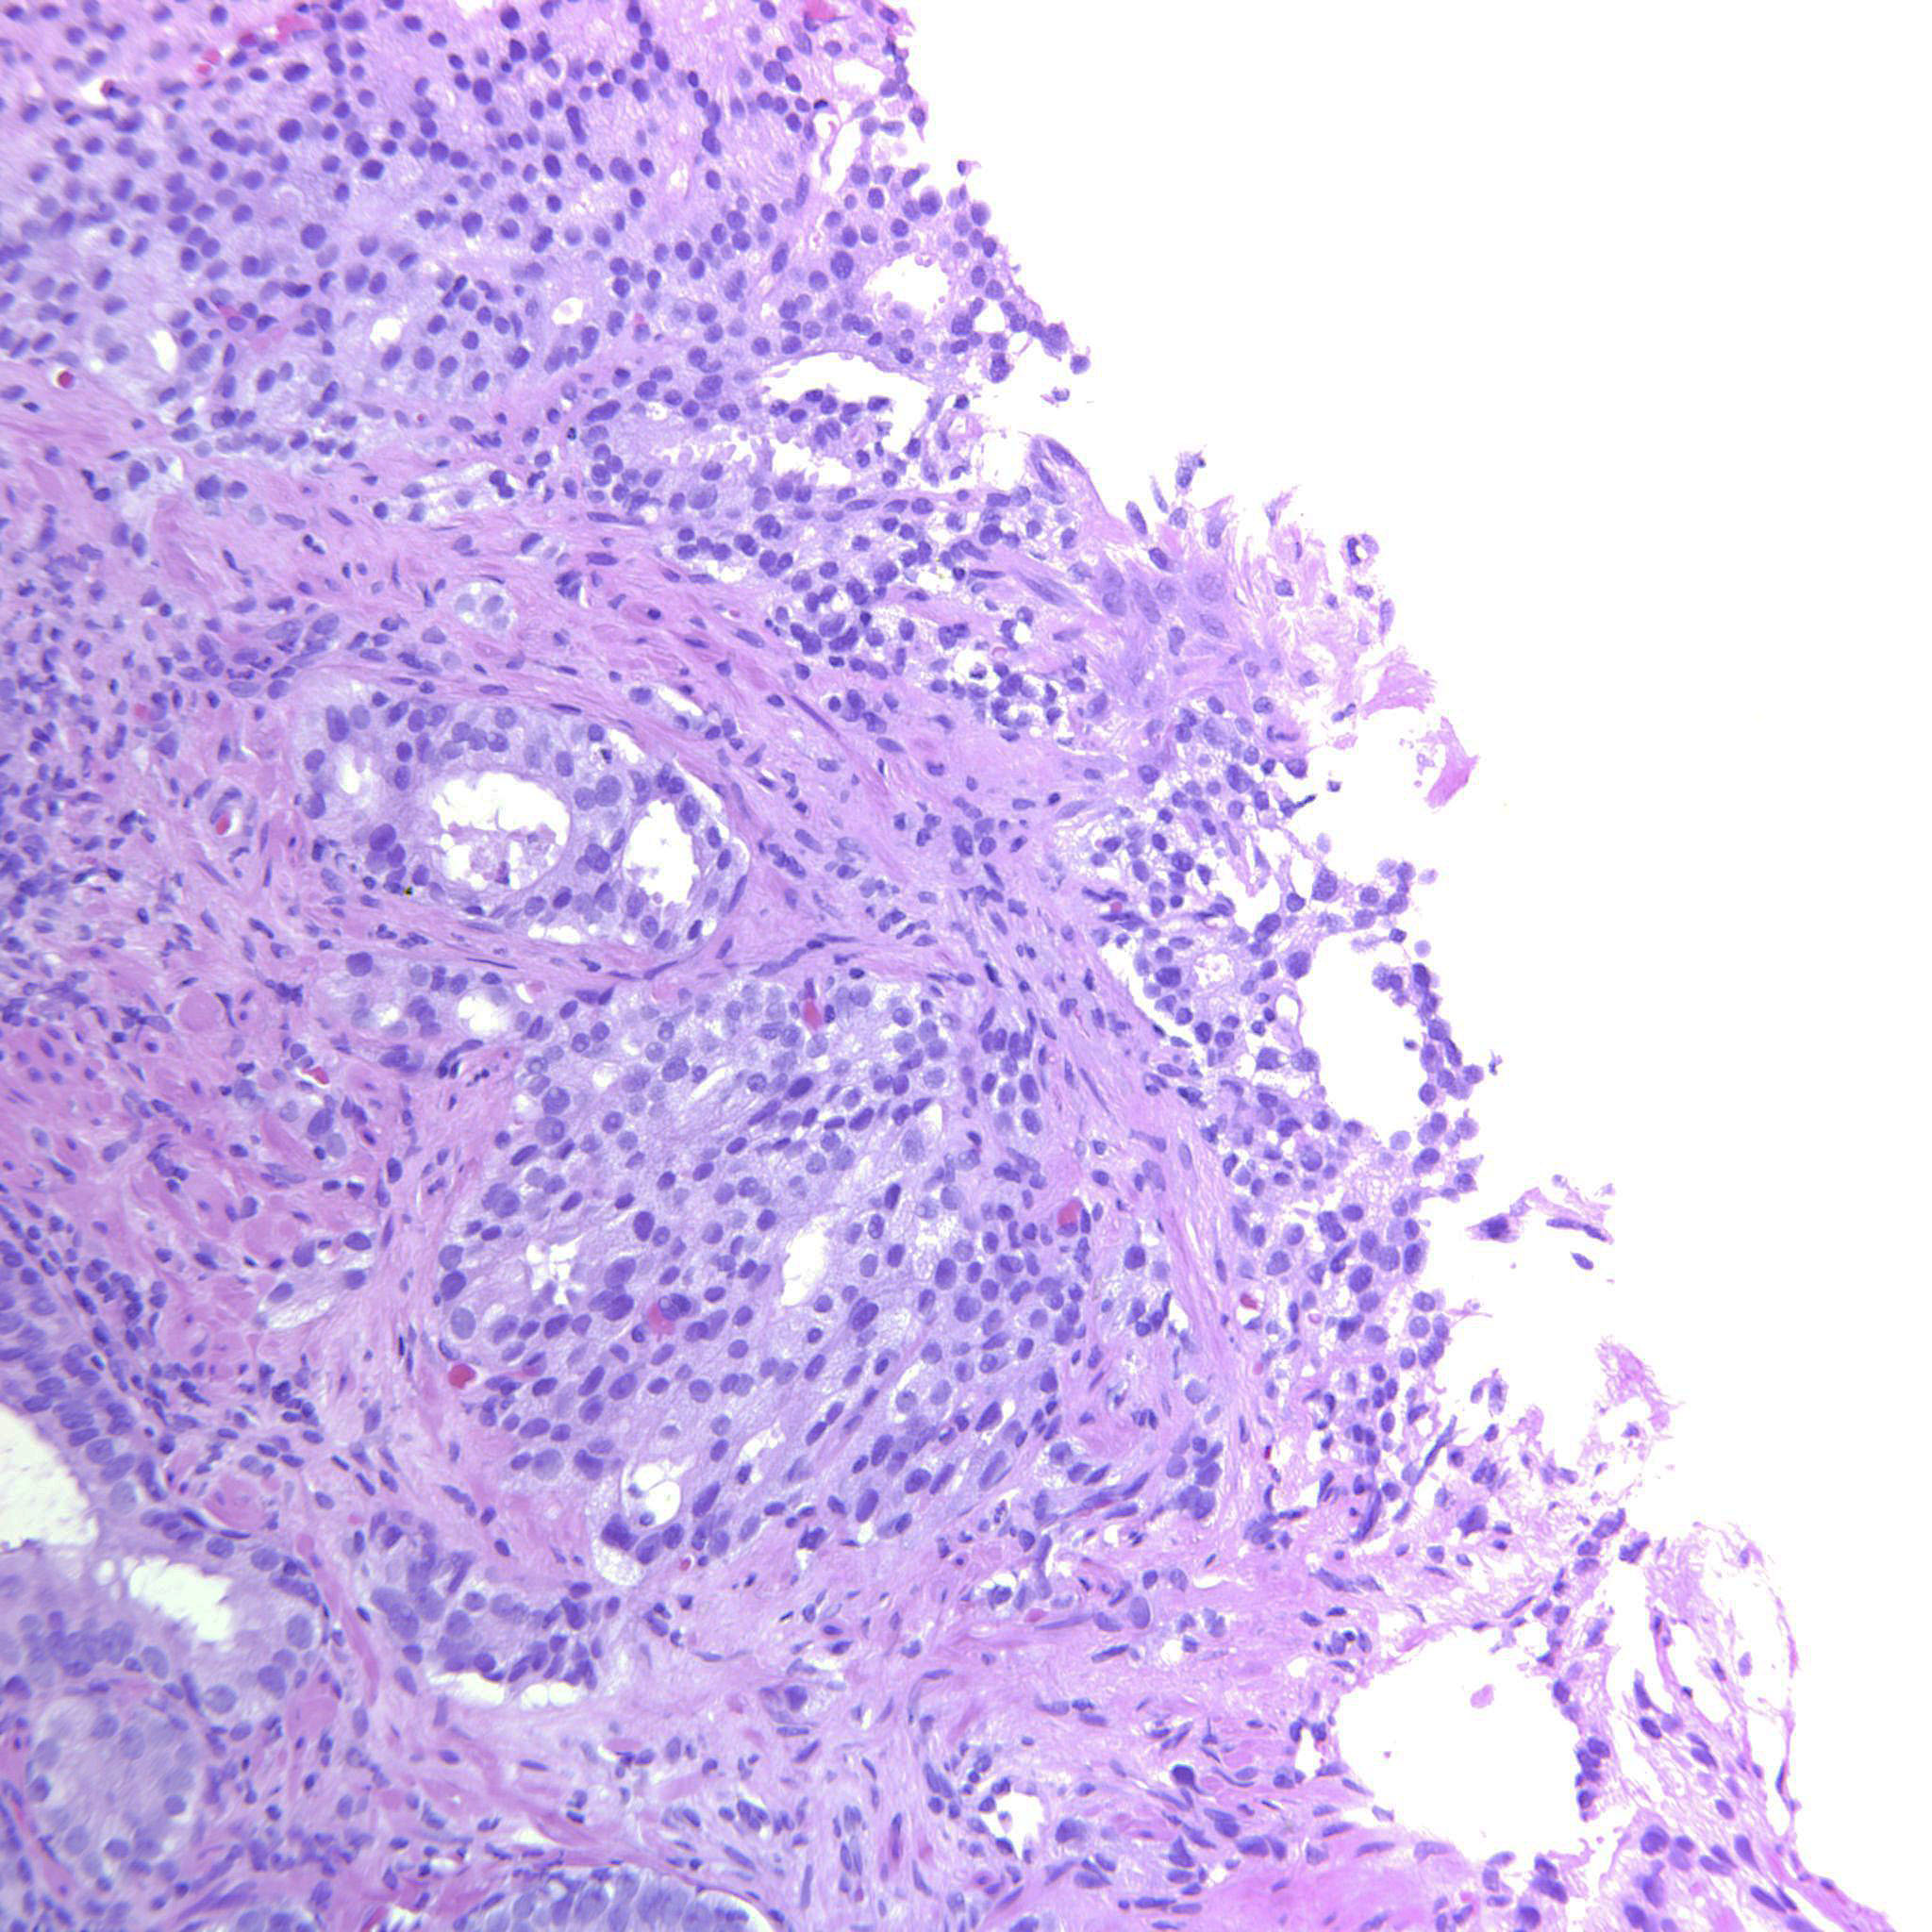

Consensus grade: GS 4+4=8 (ISUP 4)

Case description (by case creator):

Large cribriform sheets and also tightly packed poorly formed glands. Some seem to be solid nests or single cells but not convincing for GP5.